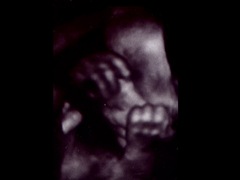

最近滿7個月時,醫師一直推薦我們可以試試看4D超音波。可以將肚子內的嬰兒,以立體方式呈現。其實沒什麼特別,而且產檢基本上還是以傳統2D方式進行,所以說穿了,這也只不過是醫院要多賺錢的另一種手法而已。

但身為父母親,總會想知道小孩像誰多一點,眼睛像誰?鼻子像誰之類的。畢竟基因真的是相當奇妙的東西。

照4D跟2D的機器是一樣的,過程都一模一樣。但因為要取得更多影像,時間會照得久一點。醫院本身相當貼心的把這次4D的過程,同步錄了一張DVD送給我們。或許日後可以拿來當小孩的成年禮,希望到時不會嚇到他。

他似乎真的很不喜歡照相,剛開始拍時,手是一直遮著臉,怎樣都不給看。不管醫生、護士,甚至是老媽的呼喊,都無效。最後還是老爸出馬才有用啦,他可是賞了臉,挪動了手勒!

目前看來,一切都正常,越來越期待1月的來臨了!